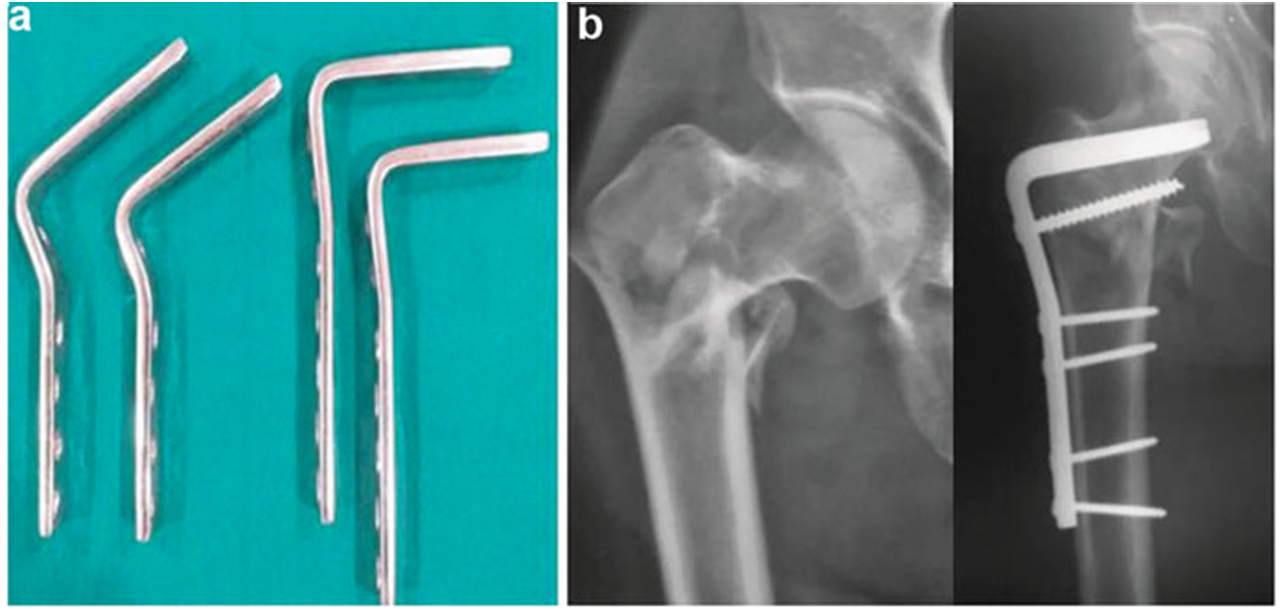

髁钢板

1977年,Müller等学者与AO/ASIF研究组共同开发了髁钢板(condylar blade plate)。这种静态植入物显著提升了固定结构的稳定性,其后续改良极大改善了转子间骨折的治疗效果。95°髁钢板在股骨转子间骨折治疗中表现出色,其通过间接复位与内固定技术有效缩短手术时间并减少术中出血,同时促进早期康复并降低并发症发生率(图4)。

图4(a) 髁刃钢板实物;(b) 术后X线显示固定效果